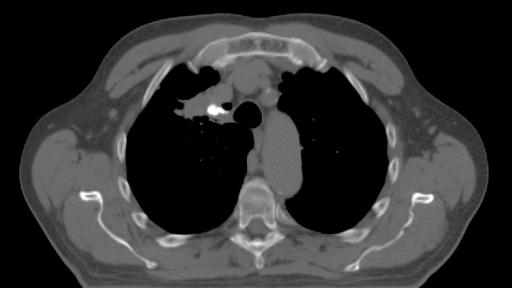

BioXmark® (1mL) is indicated for use to radiographically mark soft tissue in or adjacent to malignant tissue in the thoracic region during a surgical procedure for at least two months after placement. BioXmark® is injected via very thin needles (endoscopically or percutaneously) and provides visibility of the target throughout the treatment. It is biodegradable and is completely resorbed within a few years.

BioXmark® is visible on x-ray, CT, CBCT, fluoroscopy, MRI and ultrasonography enabling multi-modality image-guided planning and treatment, which is becoming the standard treatment approach in radiotherapy in hospitals across Europe. Compared to conventional metal based soft tissue markers, BioXmark® creates limited artefacts in CT and MRI and induces minimal dose perturbation in proton therapy. Moreover, BioXmark® has no sharp edges, which tend to cause migration of conventional metal based markers in patients.

"We have tested BioXmark® in patients with lung cancer and found that it is easy to work with and clearly visible. Markers were injected in tumour tissue, lymph nodes and lung tissue and we observed no migration from the planning CT to end of treatment ,” said Lena Specht, MD, PhD, Professor of Oncology, Dept. of Oncology, Rigshospitalet, Copenhagen University Hospital, Denmark. “ We have also tested BioXmark® in patients with oesophageal cancer and saw no migration between planning CT to end of treatment, and again, BioXmark® was well tolerated."